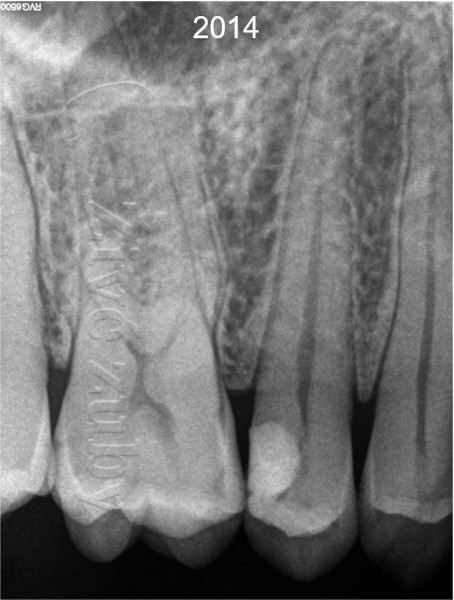

Pokus o záchranu zubu se zachováním vitality. Obvykle k tomu postačuje zhotovení zubní výplně. Odhadovaná cena ošetření je cca 1000 – 2000Kč (dle rozsahu). První výplň bylo nutné vyměnit cca po 10 letech. V případě selhaní je záložní plán endodontické ošetření (viz varianta B).

Při pečlivém stanovení vitality zubu je úspešnost biologicky orientovaného ošetření vyšší ale i výrazně levnější. Jednoduší postupy jsou prediktabilnejší a dostupnější jak pro lékaře, tak i pro pacienta. Šetrný přístup z dlouhodobého hlediska má výhodný cost-benefit (šetří zuby pacienta i jeho peněženku). Odsunutí náročnějšího ošetření přináší výhodu modernější medicíny. Odklad jen o několik let přináší pokrok jak v materiálech, tak i dovednostech ošetřujícího lékaře. V případě selhání ošetření existuje záložní plán na záchranu zubu.